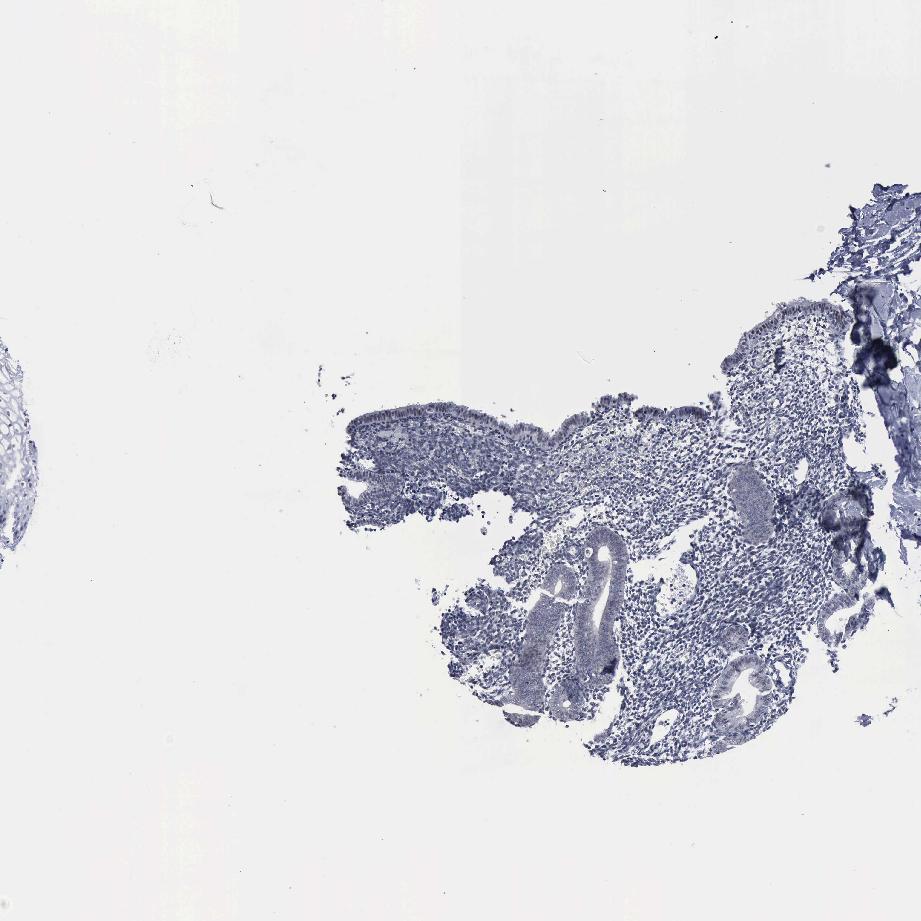

ENDOMETRIUM 1 - Antibody stainingi

Antibody staining in the annotated cell types in the current human tissue is reported as not detected, low, medium, or high, based on conventional immunohistochemistry profiling in selected tissues. This score is based on the combination of the staining intensity and fraction of stained cells.

Each image is clickable and will lead to virtual microscopy that enables deeper exploration of all samples and also displays staining intensity scores, fraction scores and subcellular localization as well as patient and tissue information for each sample.

Antibody HPA000807Antibody HPA001063

Cells in endometrial stroma Not detectedNot detected

Glandular cells Not detectedNot detected

ENDOMETRIUM 2 - Antibody stainingi